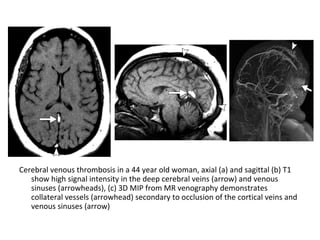

Cerebral venous thrombosis in a 44 year old woman, axial (a) and sagittal (b) T1

show high signal intensity in the deep cerebral veins (arrow) and venous

sinuses (arrowheads), (c) 3D MIP from MR venography demonstrates

collateral vessels (arrowhead) secondary to occlusion of the cortical veins and

venous sinuses (arrow)